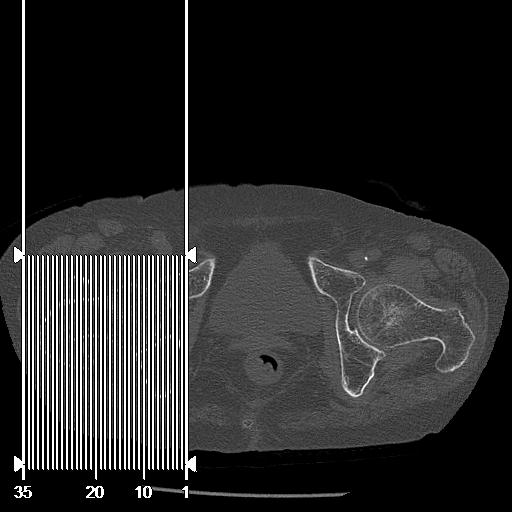

100703 1/27 両股正面+軸 1/29 両股正面+軸 94歳女性 パンソンロン